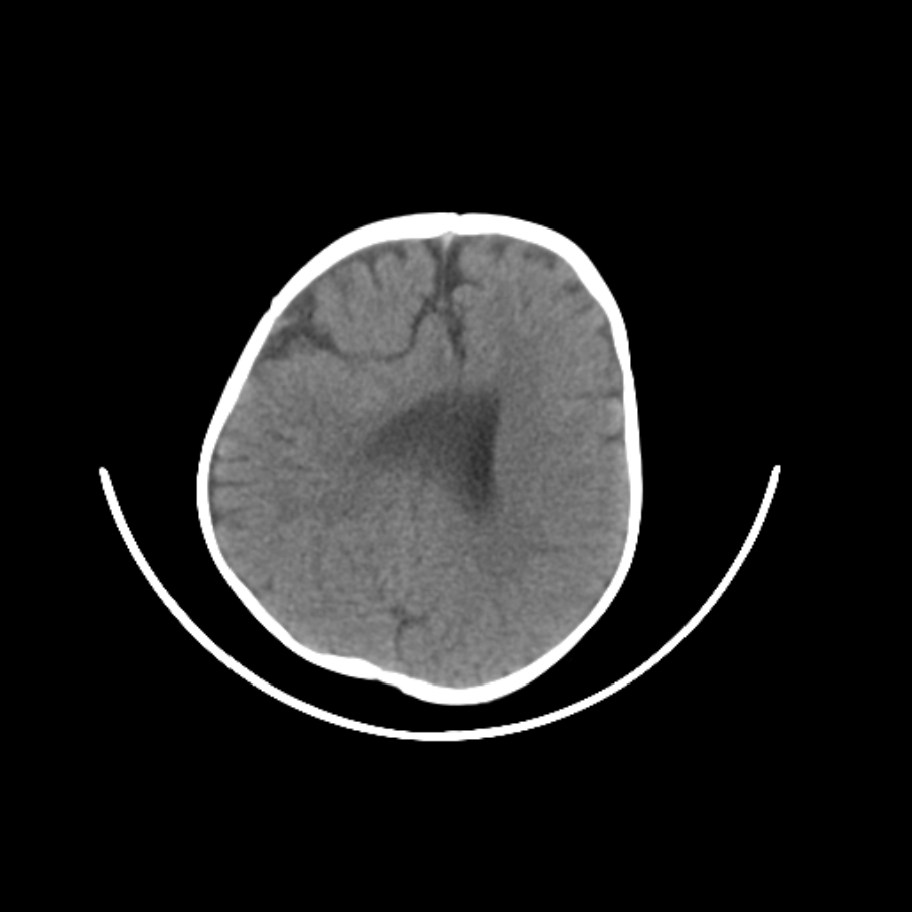

以下是引用随光逐影在2009-4-8 7:51:00的发言:[br]1)透明隔缺如(视-隔发育不良?)。2)右侧脑裂畸形。3)右侧幕上半球脑萎缩。